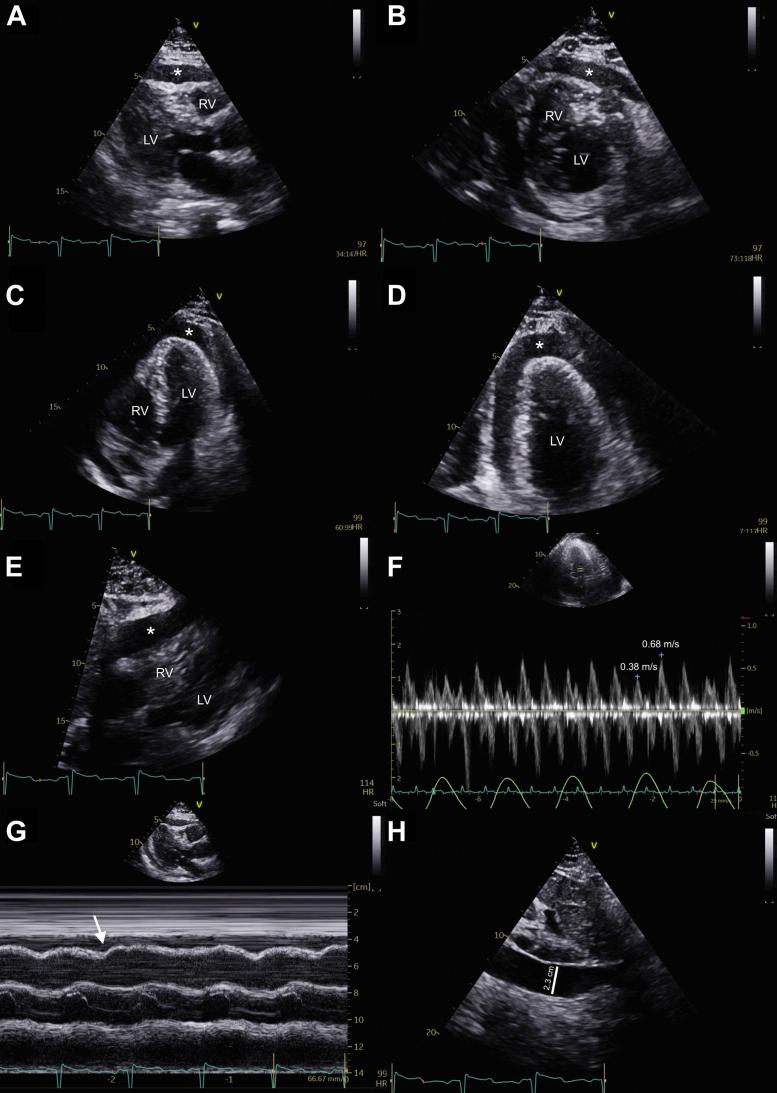

The authors present a very rare case of bacterial purulent pericarditis due to 2 weeks following an endobronchial ultrasound bronchoscopy. On his presentation, he was in cardiac tamponade, for which he underwent an emergent pericardiocentesis with purulent drainage. Similar organisms grew in his left pleural effusion. ().

作者报告了一例非常罕见的细菌性化脓性心包炎病例,该病例发生在支气管内超声支气管镜检查后2周。患者就诊时处于心脏压塞状态,为此接受了紧急心包穿刺引流脓性液体。其左侧胸腔积液中培养出了类似的微生物。()